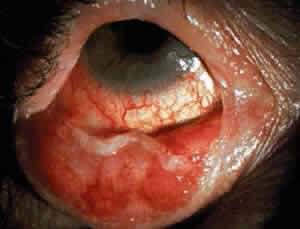

Cicatricial pemphigoid generally runs a chronic course, characterized by progressive shrinkage of the conjunctiva. When the end stage of this disease is reached, the eye lacks tears and has obliterated conjunctival fornices, ankyloblepharon, and a keratinized ocular surface epithelium. Episodes of acute disease activity may interrupt this chronic progressive course and result in rapid shrinkage of the conjunctiva.15 Acute disease activity may be precipitated by surgical procedures, including conjunctival biopsy, lysis of symblepharon, oculoplastic procedures on the eyelids, and cataract extraction. The acute manifestations consist of localized, ulcerated conjunctival mounds (Fig. 4) or diffuse, severe conjunctival hyperemia and edema (Fig. 5). Before concluding that acute inflammatory activity is caused by the disease process, it is necessary to eliminate other confounding factors such as trichiasis, exposure, or bacterial blepharoconjunctivitis.

In the early stages of conjunctival disease, granulation tissue is found beneath the conjunctival epithelium, with an infiltration predominantly of lymphocytes and plasma cells, with occasional eosinophils and relatively few neutrophils.13,26 Later, pronounced fibrosis takes place in the conjunctival stroma and is responsible for the conjunctival shrinkage that characterizes the disease.9,10 Hyperproliferation of conjunctival fibroblasts from patients with CP has been demonstrated in tissue culture.29 One study described perivascular inflammatory cell infiltration in 20% of specimens and substantial mast cell participation and degranulation.4 In addition to the chronic inflammatory cells typical of CP, conjunctival biopsy specimens from patients with acute manifestations of CP show numerous neutrophils within and beneath the conjunctival epithelium (Fig. 8).15